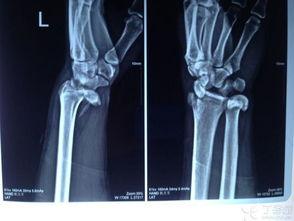

桡骨脱臼,听起来是不是很专业?简单来说,就是你的手腕关节出了点小状况,桡骨(就是手腕那根骨头)从原来的位置滑出来了。这种情况在日常生活中并不少见,比如摔跤、扭伤等。

那么,当桡骨脱臼了,我们该怎么办呢?当然是要复位!复位,就是将脱臼的桡骨重新放回原来的位置。听起来简单,但操作起来可要讲究技巧哦!